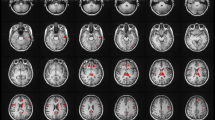

Two DKI parameters, FA and MK, were measured bilaterally in 12 brain regions (Fig. 2), including the auditory pathway and related cortex (trapezoid body, superior olivary nucleus, medial geniculate body, auditory radiation, and Heschlās gyrus), language-related cortex (middle and inferior frontal gyri, middle and superior temporal gyri, angular gyrus, and supramarginal gyrus), and learning and memory function-related regions (hippocampus). Patients over 3 years of age had significantly lower FA and MK values in 6 white matter regions. However, in 2 other white matter regions of interest (ROIs) and 2 grey matter regions, only MK was lower, with no appreciable change in FA. In contrast, the younger patients (1 to 3-year-olds) had lower FA values in 3 white matter regions but no appreciable change in MK (Table 2). Figure 3 shows that compared with the healthy controls, patients older than 3 years with brain parenchymal lesions exhibited significant differences in terms of both FA and MK in five ROIs, whereas patients with normal MRI scans exhibited significant differences in both FA and MK in only 1 ROI (the superior temporal gyrus). More regions were detected with a lower MK or FA in patients with white matter lesions than in patients with undetectable lesions. Figure 4 shows that the patients under 3 years of age with brain parenchymal lesions had significant differences only in the FA of 4 ROIs (auditory radiation, Medial geniculate body, Heschlās gyrus, and angular gyrus) and no appreciable change in MK.

Representative DKI of the ROIs. The red circle indicates the selected ROI. (A) ā angular gyrus ā” supramarginal gyrus. (B) ā middle frontal gyri ā” inferfrontal gyri. (C) ā auditory radiation ā” white matter of Heschlās gyrus ⢠middle temporal gyri ⣠superior temporal gyri. (D) ā medial geniculate body. (E) ā hippocampus. F ā trapezoid body ā” superior olivary nucleus.